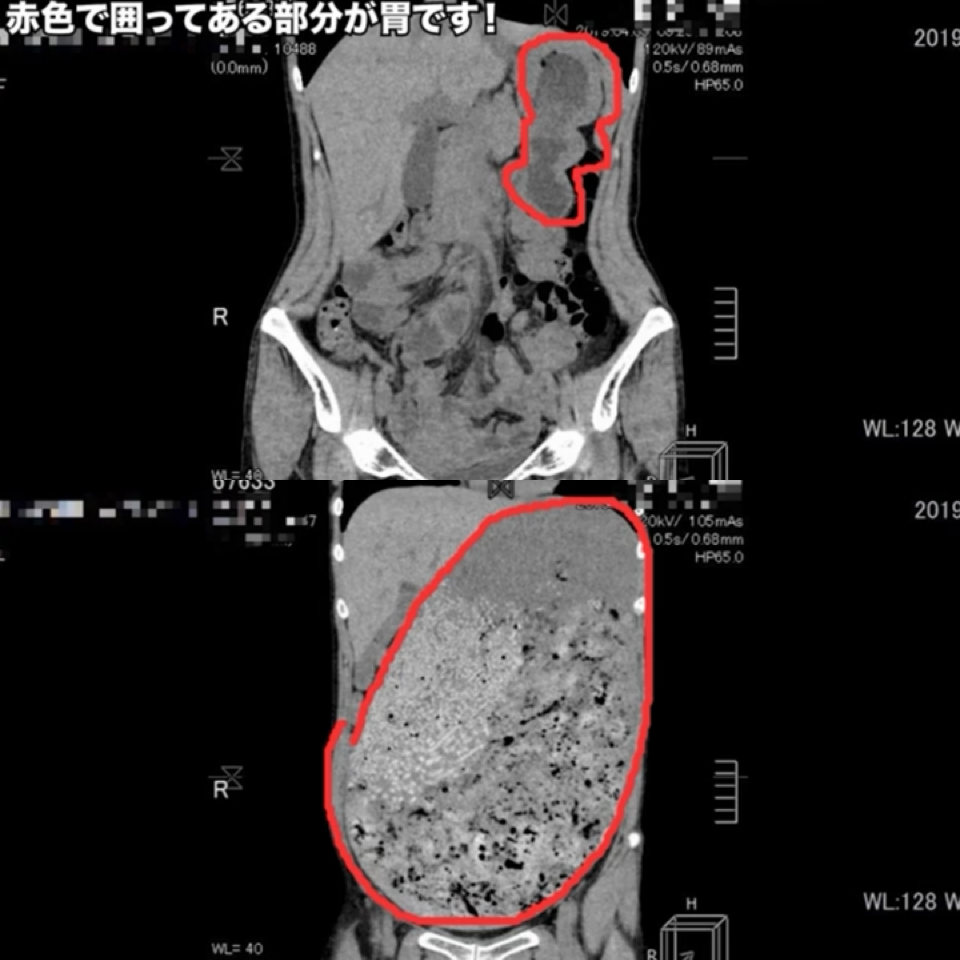

>>1

胃の壁が厚くて大食いした時の胃はゴムみたいに伸びるらしい![大食いYouTuber・はらぺこツインズ、活動休止を報告 小野あこ即時入院、小野かこ体調不良]()